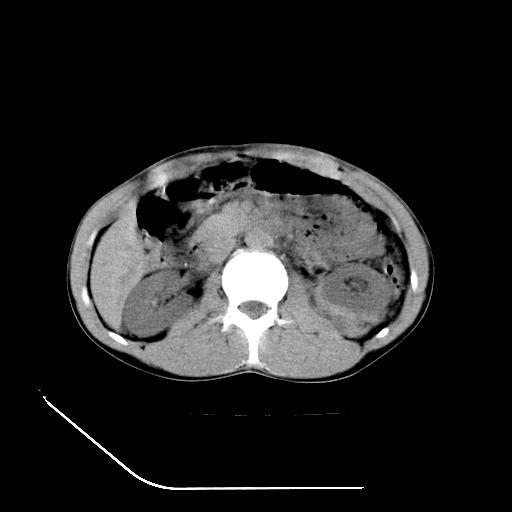

m-25y 高空堕落 12 月5号

12月7号病人尿量200ml/24h 急查双肾ct

左肾挫裂伤并肾周血肿;

肝肾间隙可见液区,建议手术探查;

支持:1、左肾挫裂伤并肾周血肿;

2、少量腹水;

3、左肾旋转不良;

4、反射性肠淤张。

除了1:左肾挫裂伤并肾周血肿;

2:少量腹水

第二次ct检查后:临床医生腹水穿刺后考虑肠系膜动脉破裂,后实行剖腹探查:于空肠距离十二指肠90cm处发现肠管破裂,破裂口较小;修补后关腹。

顺便请各位老师认真看看7号片

各位老师觉得胆囊是不是有点积血。我在原始片看胆囊密度不均,似有小液平面

再有就是支持楼主,胆囊7日片比5日片不仅增大许多,靠后下更见液液分层,应该是有积血。